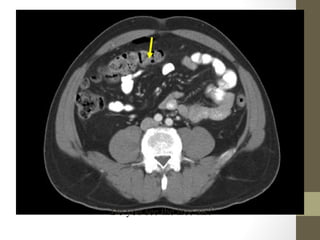

Radiology- CT Scan

diverticulitis, abscess, mesenteric ischemia, masses, obstruction

Sigmoid Tumor/Intussusception

Radiology- CT Scan •Detect leaking AAA (in stable patient) • Evaluate for renal calculi, appendicitis, perforation (free air), diverticulitis, abscess, mesenteric ischemia, masses, obstruction • Sensitivity and specificity vary • Not a place for unstable patients • Contrast • PO and IV contrast in most patients • sometimes rectal contrast is helpful to look for large bowel problems (appendicitis) • In patients with renal insufficiency • give IV contrast judiciously in patients • consider ultrasound as an alternative if possible • a creatinine > 1.5 usually requires bicarbonate and fluid hydration to minimize contrast nephropathy